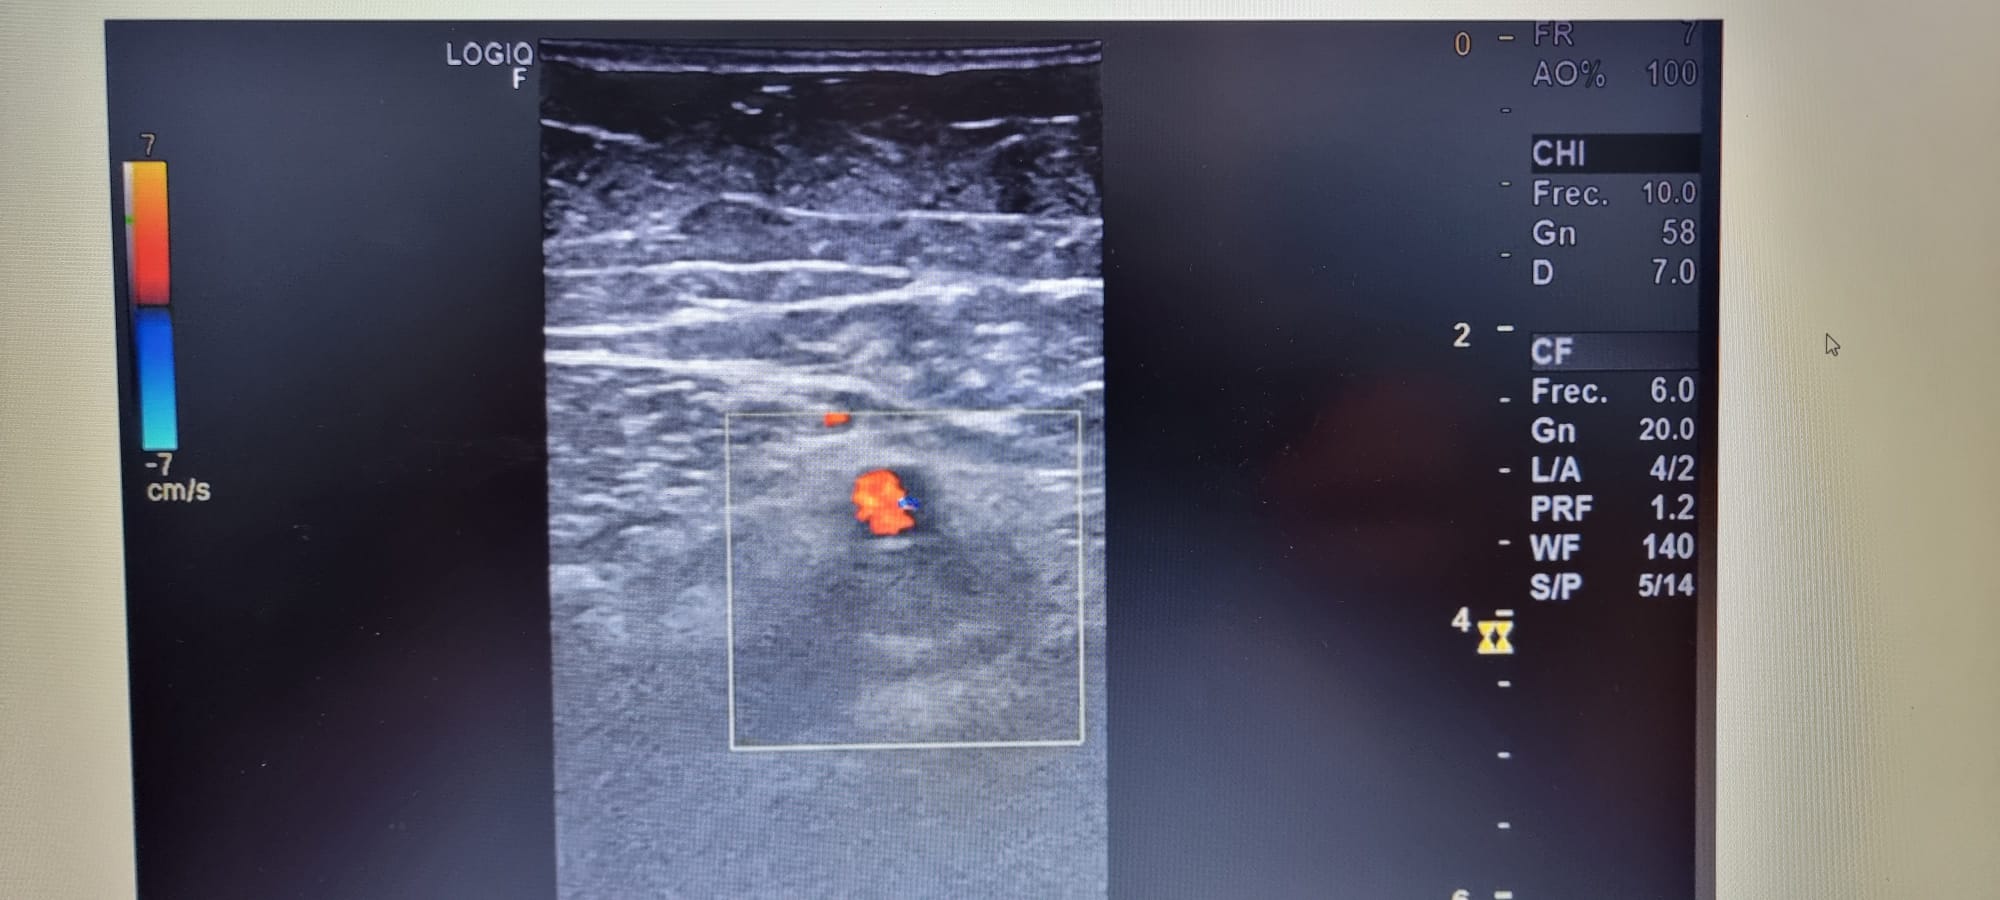

Hallazgos ecográficos

Se realiza ecografia venosa de mid evidenciándose ocupación parcial de femoral común, y segmento de femoral superficial.